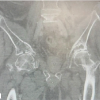

Mr. S., aged 52, was found lying beside the road in an inebriated manner, and was referred from multiple centres, leading to a 2½ week delay in treatment. X-rays showed a superior type fracture of the right acetabulum (Fig. 1).,

Figure 1: (a) Three months post-operative X-ray of the pelvis (b) Immediate post-operative X-ray of the pelvis.

In addition, the patient had an non-displaced C1 fracture, which was not associated with any neurodeficit and was conserved. To better control the reduction of all the features, particularly of the anterior wall, an enlarged iliofemoral approach according to Judet and Letournel [1] was performed with partial elevation of the iliacus. Anterior superior iliac spine osteotomy was done for better visualisation of the anterior column and wall and for garnering adequate angulation for osteosynthesis. The callus at the fracture line extending intraarticularly was removed, and reduction was achieved via pressure over the iliac blade and attachment of a Schanz pin to the iliac crest to use in a joystick manner. Osteosynthesis using two 4.5 mm fully threaded cannulated screws was performed with iliac blade fixation (Fig. 1). In the post-operative course, hip mobilization was started as soon as the pain subsided and continued at the patient’s residence. No ossification prophylaxis was performed apart from abundant washing of the wound with isotonic serum throughout the procedure. At 6 months after the trauma, the Merle d’Aubigné functional score was, a reliable predictor of hip function, [7] was 17.